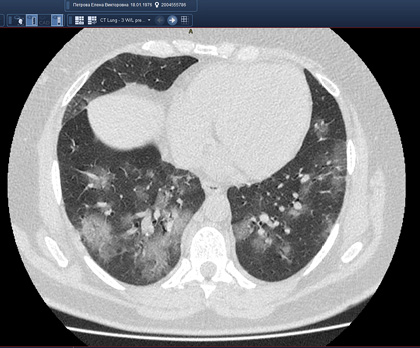

Routine clinical laboratory assays were performed in the hospital’s clinical laboratories. Clinical and laboratory information was extracted from the patients’ medical records. C reactive protein (CRP) in plasma was measured by immunoturbidimetry (Beckman Coulter, Krefeld, Germany). Interleukin-6 (IL-6) levels in plasma were measured by electrochemiluminescence (Siemens Medical Solutions Diagnostics, Siemens Healthcare, Erlangen, Germany). CT scans were read by experienced radiologists who scored results by severity using the criteria shown in Figure 1.

Figure 1. Clinical assessment of pneumonia severity based on computed tomography (CT) scores.

Scoring method: Mild (CT-1)—no more than three ground-glass opacities of <3 cm maximum diameter. Moderate (CT-2)—more than three ground-glass opacities; less than 50% involvement by visual assessment. Medium-heavy (CT-3)—ground-glass opacities and pulmonary consolidation; 50-70% involvement by visual assessment. Severe (CT-4)—diffuse ground-glass opacities with or without consolidation; more than 75% involvement by visual assessment.